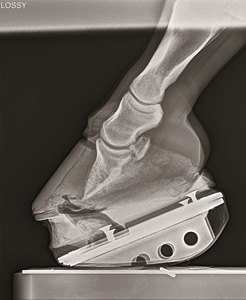

There are three types of laminitis, and all impair the structure and function of the horse's foot. This research provided a snapshot of the active pathways and functions of the hoof, with a focus on supporting limb laminitis—the laminitis to which 2006 Kentucky Derby Presented by Yum! Brands (G1) winner Barbaro succumbed.

The first related to keratin, an important structural protein that helps maintain the structural integrity of materials like hair, nails, and horse hooves. This study was one of the first to examine the changes in the keratin family as laminitis progresses. Some of the keratin-related genes and regulation of the cell's manufacturing process started to diminish as the disease began. Researchers compared this change to when a car gets a flat tire; it may still be running but it loses appropriate function and slows down.

Another type of cell machinery often studied in laminitis are a class of enzymes called metalloproteinases, which are enzymes that help maintain the cytoskeleton. These enzymes must maintain a careful balance. Hooves must be able to grow and not break down under the weight of the horse, which requires a balance of remodeling and building tissues within the hoof. When the metalloproteinases become too active, the hoof begins to lose structural strength. One previous theory for treatment was to stop these enzymes from becoming too active. Targeting these enzymes, however, might also stop hoof growth and likely lead to further issues.